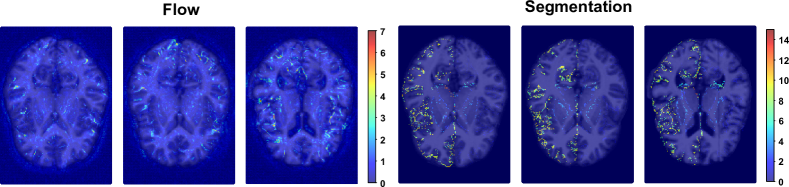

Refer to caption

Figure 4: Stability assessment over 10 predictions on different test samples from the OASIS registration task. Left: variance for the flow, right: variance for the corresponding segmentation masks – using NCA-Morph107×7superscriptsubscriptabsent7710{}_{7\times 7}^{10}.

We computed the standard deviation of the ten resulting flow fields, offering a measure of variability in the spatial transformations generated during the registration process. Additionally, we assessed the standard deviation of the corresponding segmentation masks, shedding light on the uncertainty associated with our model’s performance. Figure 4 clearly indicates the reliability and consistency of our NCA-Morph in handling registration tasks.